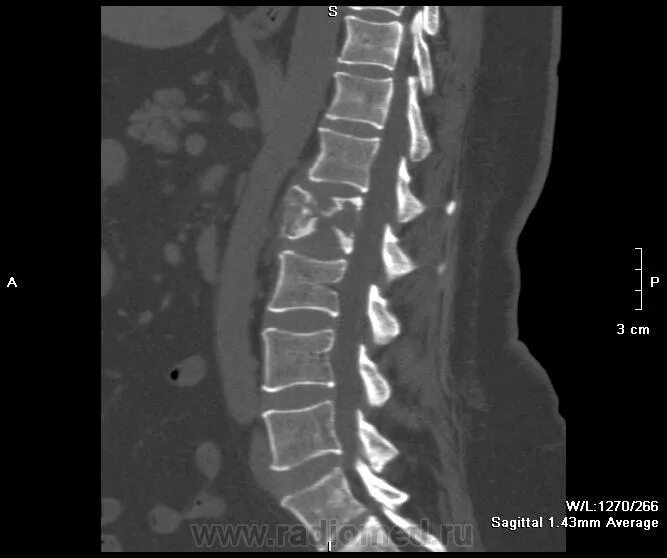

Остеосклероз грудного отдела